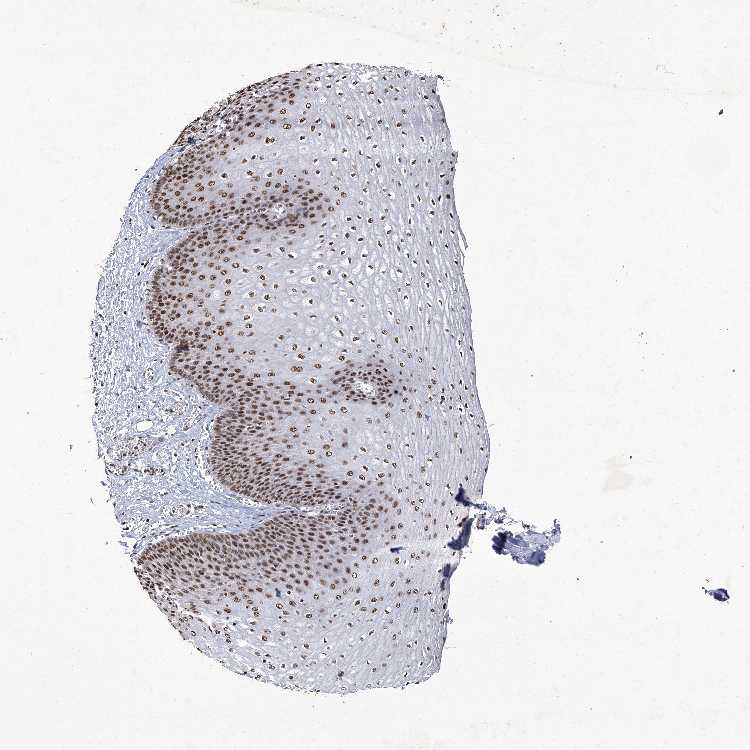

ESOPHAGUS - Antibody stainingi

Antibody staining in the annotated cell types in the current human tissue is reported as not detected, low, medium, or high, based on conventional immunohistochemistry profiling in selected tissues. This score is based on the combination of the staining intensity and fraction of stained cells.

Each image is clickable and will lead to virtual microscopy that enables deeper exploration of all samples and also displays staining intensity scores, fraction scores and subcellular localization as well as patient and tissue information for each sample.

Antibody CAB032824

Squamous epithelial cells High